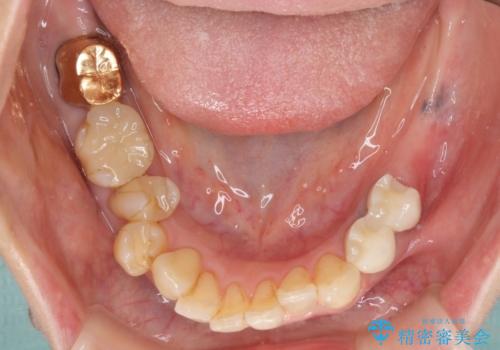

- 奥歯が痛いことを主訴にご来院された患者様です。入院してしまい、治療を2年間放置してしまったとのことでした。

左上は、抜歯とブリッジ治療を行いました(抜歯前に医師と対診)。

左下は、現在も抗がん治療を続けているため、観血的処置(インプラントなどの外科)はなるべく避けたいとのことで入れ歯を希望されました。それに伴い、入れ歯を支える歯のクラウンやりかえも行いました。

患者様はインプラント等の外科処置は希望されなかったため、セラミックと義歯で治療を行いました。

義歯を製作する際は、支えとなる歯の治療も同時に行うことで、義歯の製作が容易になります。

今回もそのように製作したところ、適合がよく安定のよい義歯になりました。患者様本人も使っていて全く痛くないとのことで、追加の調整もなく使用して頂いてます。患者様には、大変満足して頂きました。